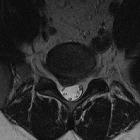

Disc protrusions are a type of disc herniation characterized by protrusion of disc content beyond the normal confines of the intervertebral disc, over a segment less than 25% of the circumference of the disc. The width of the base is wider than the largest diameter of the disc material which projects beyond the normal disc margins. The protrusion must not extend above or below the relevant vertebral endplates .

A disc protrusion is also described in terms of its axial position, into central, subarticular, foraminal, extraforaminal, or anterior locations .